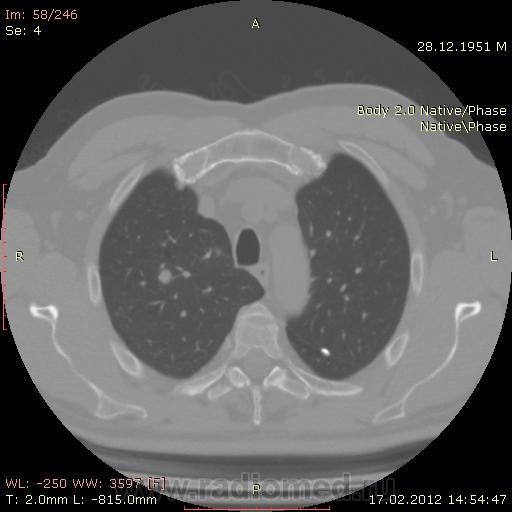

КТ.

В феврале 2012 года при очередном флюрографическом обследовании были обнаружены изменения в лёгких. По собственной инициативе было сделано КТ лёгких.